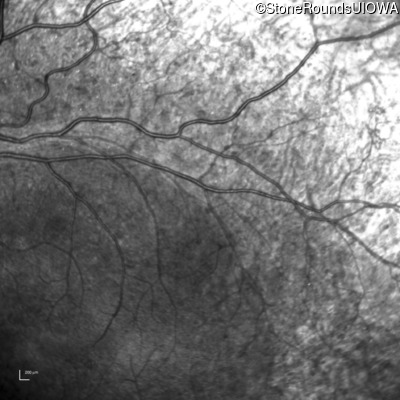

Infrared Fundus Photograph - Left - 20/20 -1

Exemplar